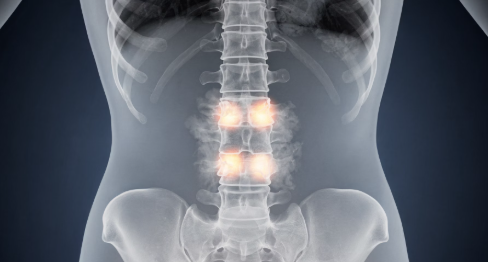

강직성 척추염은 척추와 천장관절(골반과 척추가 만나는 부위)에 만성 염증이 발생하는 자가면역성 질환입니다.

염증이 반복되면 뼈가 굳고 서로 붙으면서 척추 움직임이 제한될 수 있습니다.

14. 척추 변형

15. 강직(뼈가 붙는 현상)